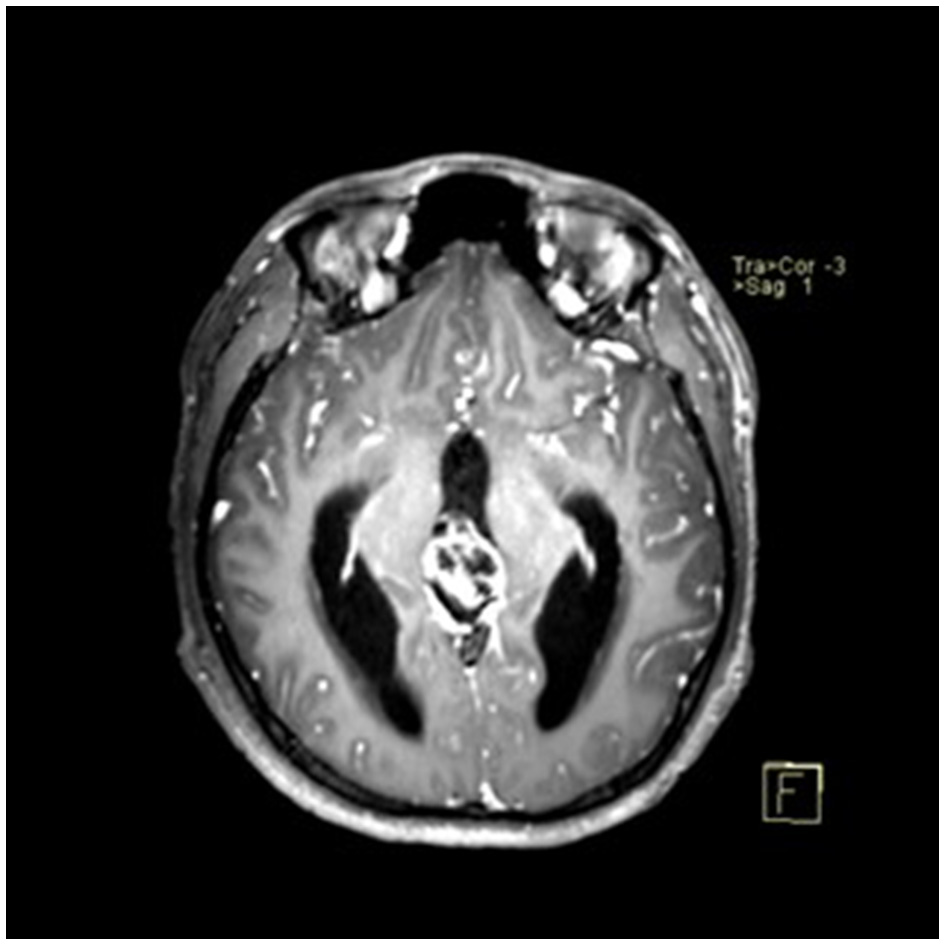

A 22-year-old male presented with intermittent dizziness and headache lasting for 2 weeks. MRI at admission revealed a cystic mass in the pineal region, accompanied by supratentorial hydrocephalus (Figures 3–5). No surgical contraindications were identified. After discussion with the patient's family, neuroendoscopic resection was performed via the Transfrontal-Transventricular-Transforaminal Approach. Intraoperatively, a 20 × 20 mm soft, well-vascularized tumor was found obstructing the cerebral aqueduct. The lesion had well-defined margins and was carefully dissected from surrounding adhesions, preserving adjacent veins and brain tissue. Macroscopic total resection was achieved en bloc (Figures 6–8). Postoperative day 1 MRI confirmed complete tumor removal and resolution of hydrocephalus (Figures 9–11). Postoperatively, no complications were observed. However, due to personal reasons, the patient was discharged on postoperative day 11. Histopathology confirmed a mixed germinoma. No recurrence or surgery-related complications were noted during follow-up.

Figure 3

Preoperative contrast-enhanced MRI (axial view) showing a cystic-solid mass in the pineal region with supratentorial hydrocephalus.